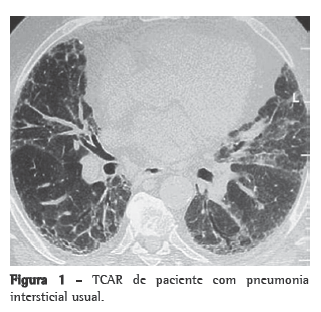

O diagnóstico histológico de PIU baseia-se em uma série de características de distribuição da doença, definindo um padrão histopatológico.(23) O tamanho do segmento de tecido pulmonar tem relação com a profundidade da amostra no parênquima pulmonar. A biópsia pulmonar deve apresentar a região periférica, subpleural, como a região mais central ou medular do pulmão. Outra recomendação é obter a amostra dessa transição entre a região nitidamente doente visualizada na TCAR e a região de aspecto aparentemente normal.(24) A TCAR permite uma ótima avaliação de todo o parênquima pulmonar, sendo rotina da avaliação inicial das doenças pulmonares intersticiais.(25) Hoje, utiliza-se a TCAR como exame de rotina no pré-operatório de qualquer biópsia cirúrgica do pulmão (Figura 1).

A TCAR permite, com razoável precisão, selecionar os locais ideais para a biópsia com estágios distintos da doença no parênquima pulmonar.